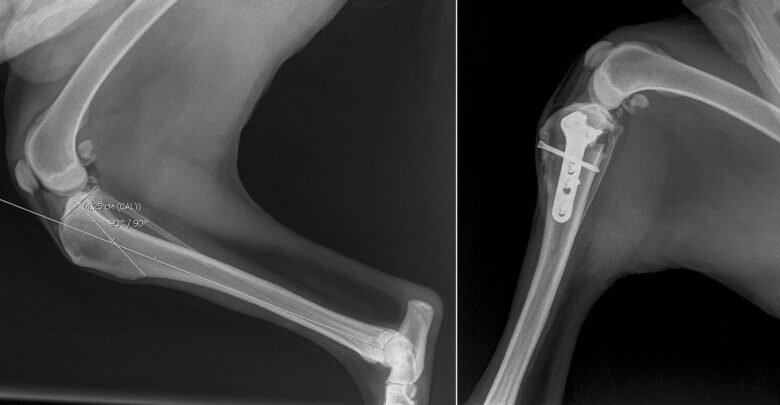

Операция по исправлению разрыва CCL называется TPLO, или остеотомией с выравниванием большеберцового плато. Эта операция требует специальной подготовки, и доктора рекомендуют проводить ее в специализированной больнице.

Операция TPLO изменяет биомеханику колена, поэтому собака все еще может использовать конечность без CCL. При операции меняется угол верхней части большеберцовой кости (голени), разрезая кость и вращая ее, чтобы другие мышцы, поддерживающие колено, могли взять на себя функции CCL.